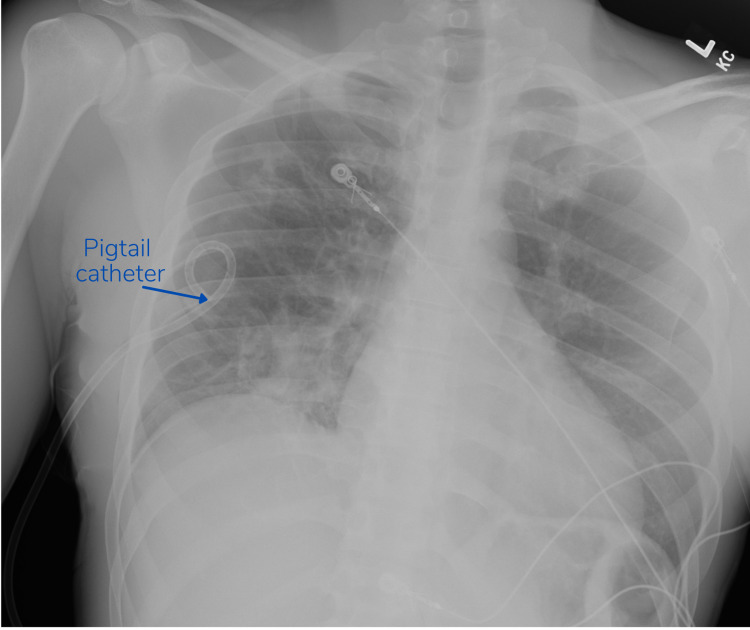

A pigtail catheter was promptly placed using local anesthesia. The patient’s breathing improved significantly. A follow-up chest radiograph two hours and twenty-five minutes later demonstrated resolution of the pneumothorax [Figure 2].